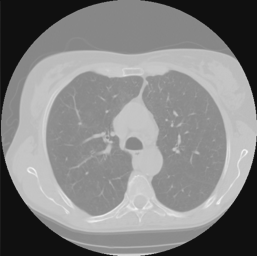

III-C2 Unsupervised Learning

To validate and evaluate the generalization of the proposed method, we adopt the network, trained on lung CT data, on the Zubal’s phantom except lung position. Fig 10 and Table II demonstrate the experiment results.

We can see the process unsupervised training have significant effect in eliminating the artifacts introduced by over fitting (fig 10 row1) and make the edges in image slightly sharper (fig 10 row2). And the data fidelity implied in loss ensures the image quality not to degrade in training (fig 10 row3). Like the results for lung CT data, our after trained network’s results have less streaking artifacts than FBP results and cartoon-like artifacts than SART-TV results. The quantitative metrics gives the same conclusion. So the after train proposed network can be transfer trained flexibly in different scanning scenes.

Refer to caption

TABLE II: Quantitative Comparsion for FBP, SART-TV and Proposed Method for Zubal CT dataset (40 slices)

FBP SART-TV Proposed

avg. PSNR(dB) 24.88 28.08 36.33

avg. SSIM 0.9598 0.9523 0.9838